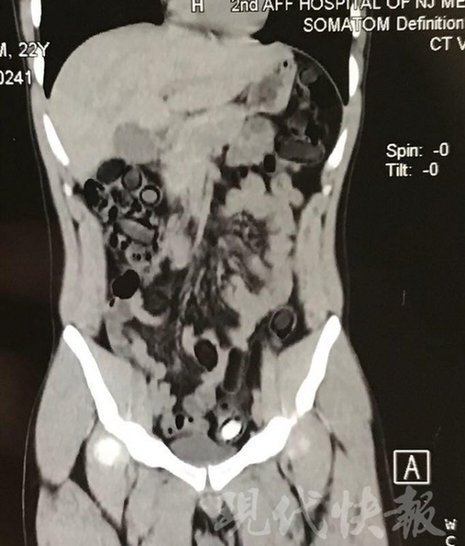

小伙體內(nèi)藏毒300余克 CT掃描圖密密麻麻全是蠶蛹

警方供圖

由于毒品在體內(nèi)一旦泄露有可能致命,警方第一時間將阿永帶到醫(yī)院進行檢查。CT 掃描的結(jié)果顯示,阿永體內(nèi)布滿了密密麻麻的白色圓柱狀固體,就像一粒粒的蠶蛹。在南京市公安局鼓樓分局二板橋派出所,阿永分四次排出了毒品,毛重369.99克。經(jīng)訊問,阿永交代了自己全部的犯罪事實。目前,阿永已被刑事拘留。